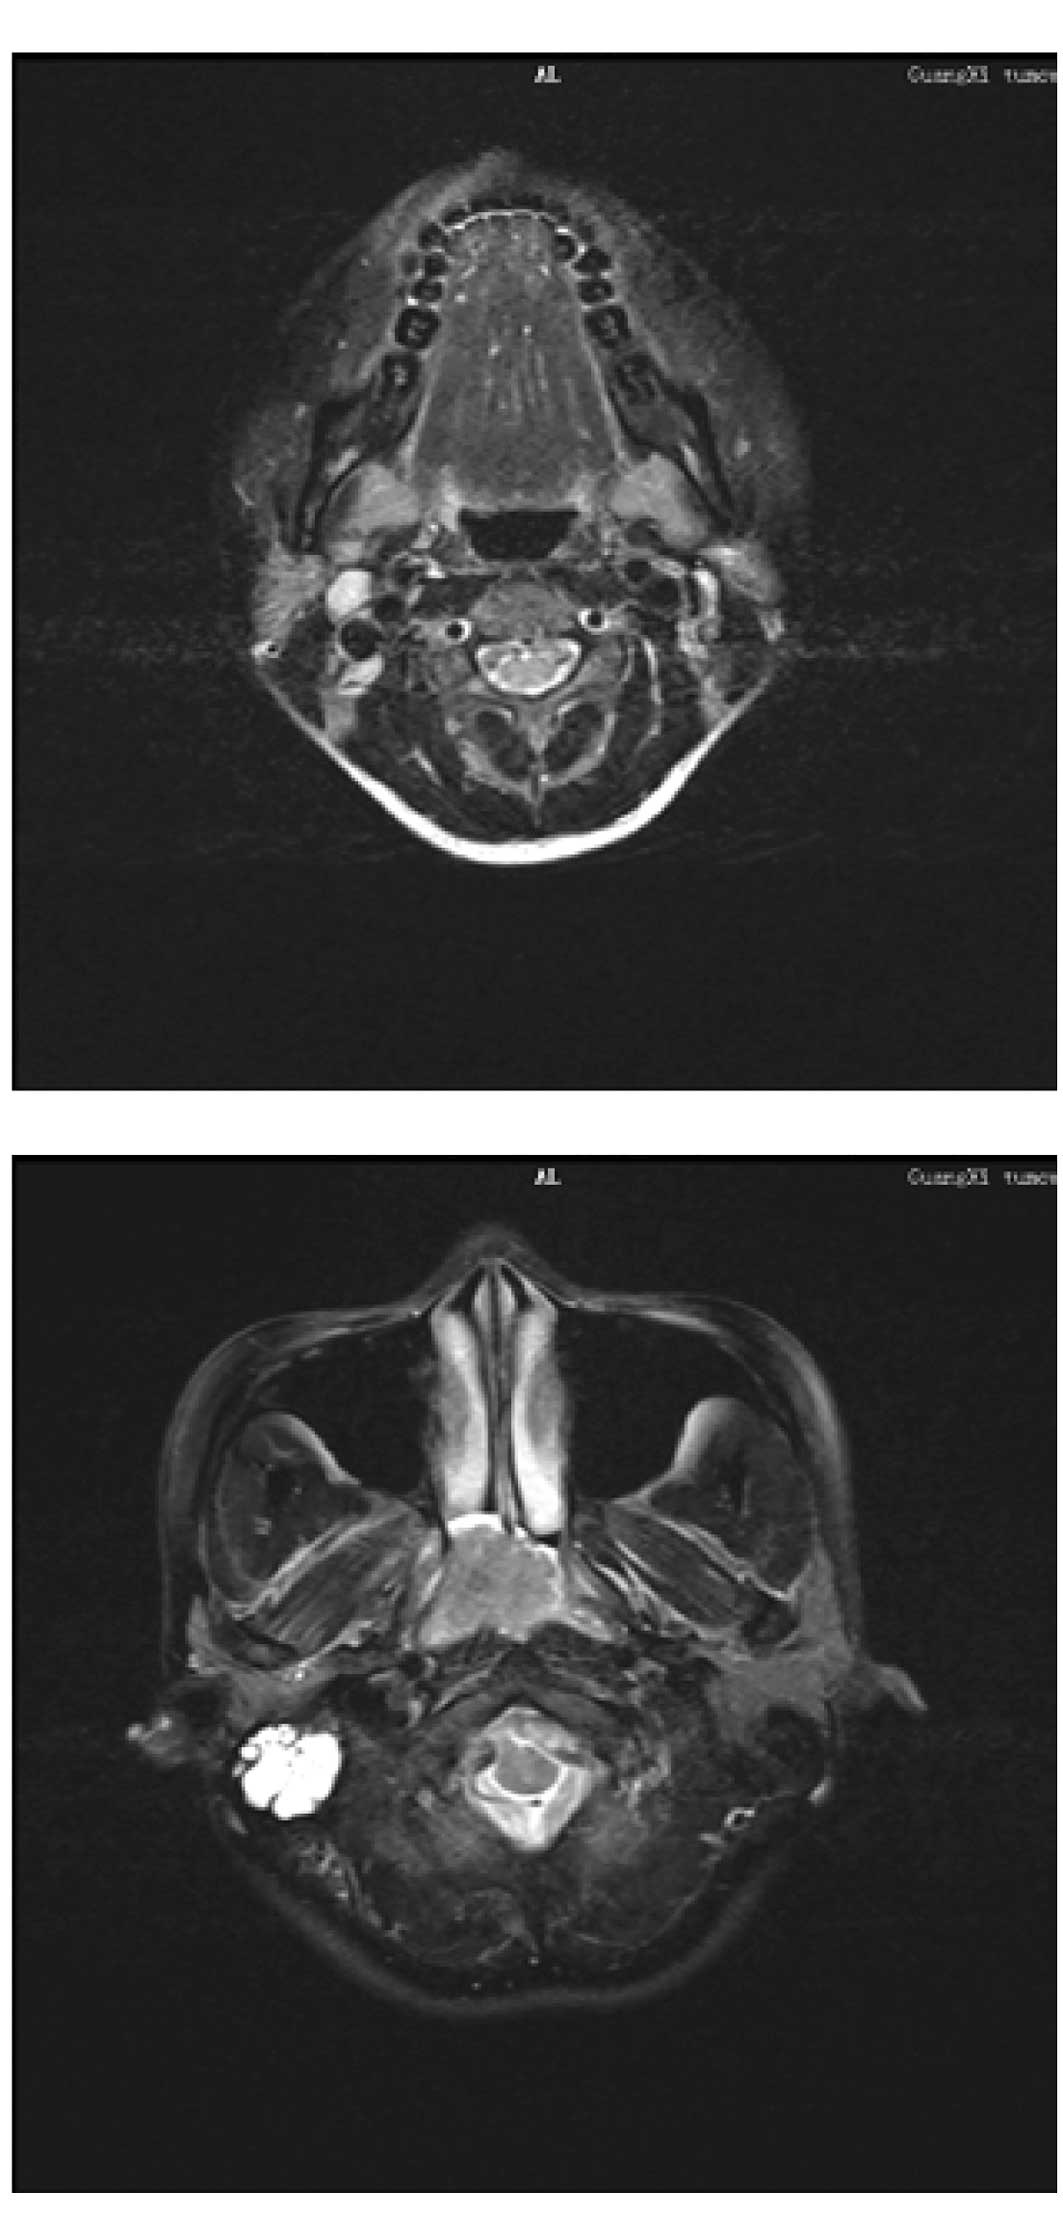

Nasopharyngeal carcinoma

Three days following surgery, the patient

experienced epistaxis and was sent for an endoscopic nasopharyngeal

examination. A mass with active mucosal bleeding was found and

biopsied (Fig. 2). Histopathology

revealed a non-keratinizing undifferentiated carcinoma. MRI showed

an enlarged lymph node in region II of the right neck and an

invasive mass in the parapharyngeal space (Fig. 3A and B). The patient was diagnosed

with nasopharyngeal carcinoma, T2N1M0/stage II (UICC, 2002).